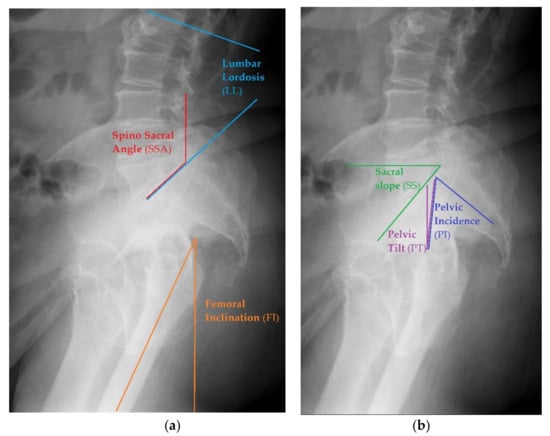

Before starting the operation, proper planning should be done. Normally, the whole process is done based on antero-posterior pelvic X-ray. In case of any suspicion of abnormalities with spinopelvic alignment, special lateral views could also be useful, as they allow one to perform measurements of more sophisticated parameters of pelvic alignment. This should visualize a part of the body from L1 to the proximal femur, including the pelvis. Example of such X-rays are seen in Figure 1.

Examples of different pelvic measurements performed on lateral X-rays of the pelvis with lumbar spine view. (a) Spino Sacral Angle, Lumbar Lordosis and femoral Inclination presented on lateral X-ray. (b) Sacral Slope, Pelvic Incidence and Pelvic Tilt presented on lateral X-ray.

- Sacral Slope (SS)—to measure this angle, one needs to draw the straight line of the S1 superior endplate and a leveled line at a right angle to the gravitational force direction (horizontal reference line) [30]. The normal value ranges between 32 and 49° [31].

- Pelvic Tilt (PT)—an angle between the reference vertical line and the line joining the middle of S1 upper endplate and the center of the femoral head. The normal value ranges from 7 to 19° [31].

- Pelvic Incidence (PI)— the angle between the line that is formed by connecting the upper endplate of S1 (at its midpoint) to the femoral head axis. The normal value ranges from 38 to 56° [31].

- Pelvic Femoral Angle (PFA)—the position of the femur in relation to the pelvis. It is the angle centered at the femoral head, between the mid sacral base and down femoral shaft. The normal value ranges from 1 to 17° [31].

- Lumbar Lordosis (LL)—the segmental angle of spinal segment in lordosis, measured between the line on the upper endplate of L1 and the line on the upper endplate of S1(L1 -L5). The normal value ranges from 40 to 58° [31].

- Femoral Inclination (FI)—the angle between a vertical reference line and the axis of the femur. The normal value ranges from 0 to 8° [31].

- Sacro Femoral Angle (SFA)—the angle between the line of the upper endplate of S1 and the axis of the femur. The normal value ranges from 43 to 61° [31]

- Spino Sacral Angle (SSA)—the angle between the line of the upper endplate of S1 and a reference vertical line. The normal value ranges from 119 to 133° [31].